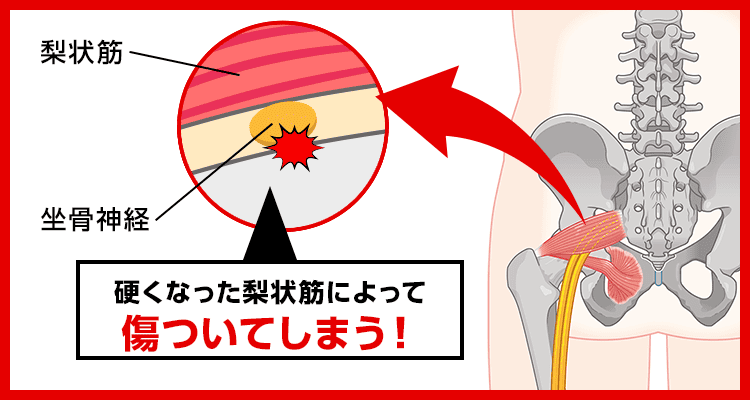

こんな痛みやしびれの原因は

梨状筋(りじょうきん)というおしりの奥の筋肉が硬くなること。

というのも

梨状筋のそばには坐骨神経が通っており、

梨状筋が硬くなると坐骨神経が圧迫されて傷ついてしまいます。

そして坐骨神経はおしり〜足先まで伸びているため、

損傷すると様々な箇所にしびれや痛みが現れるんです…